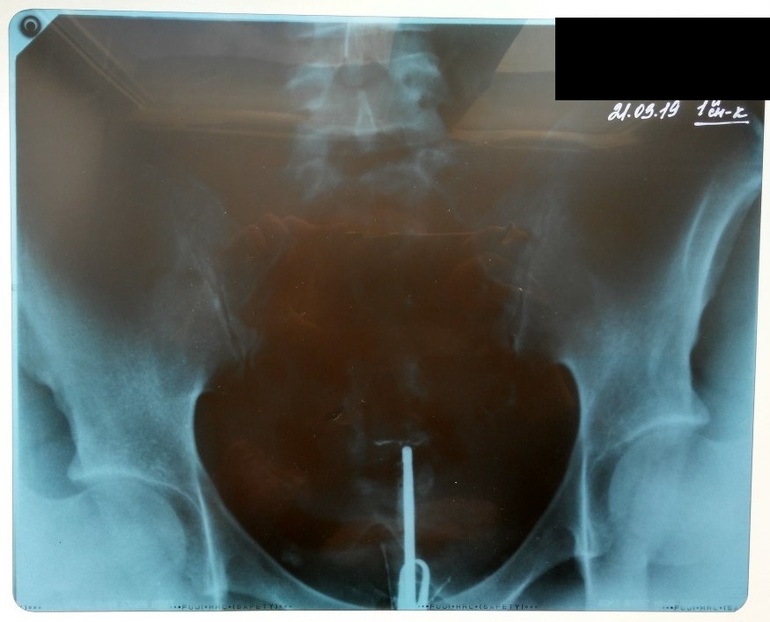

ГСГ, ЭХО, МСГ, ФертилоскопияДевочки, выручайте, у кого такое было. Вчера проходила ГСГ в стационаре . Внутримышечно поставили дротаверин, потом в рентгенкабинете укол в шейку, но когда доктор вливал раствор, он просто свободно вытекал на пеленку( Гинеколог сказал, смысла снимки делать нет. Бестолку сделали два снимка. Сегодня забрала рентген - на нем даже матки нет. В заключении - полная непроходимость. У кого было такое, что на рентгене даже матки не видно?

Может быть плохо выставили катетер? Судя по всему он даже в матку не зашел.

А на УЗИ какая у Вас картинка? Какая длина у шейки, как матка расположена?

матка у меня кзади, а вот длину шейки ни в одном протоколе УЗИ даже не нашла(